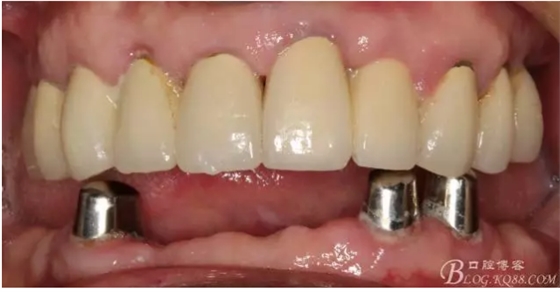

還要有足夠的牙本質(zhì)肩領(lǐng),大家現(xiàn)在可以看到患者的下頜套筒冠還是非常好的

修復(fù)后照片,

患者的口腔衛(wèi)生保持的不好,有大量的軟垢附著,

最近復(fù)查的照片,牙周維護(hù)好一些了,畢竟是一個(gè)80歲的老爺爺了,每次來(lái)拄著拐,還要跟著很多人攙扶著過(guò)來(lái)很不容易了。